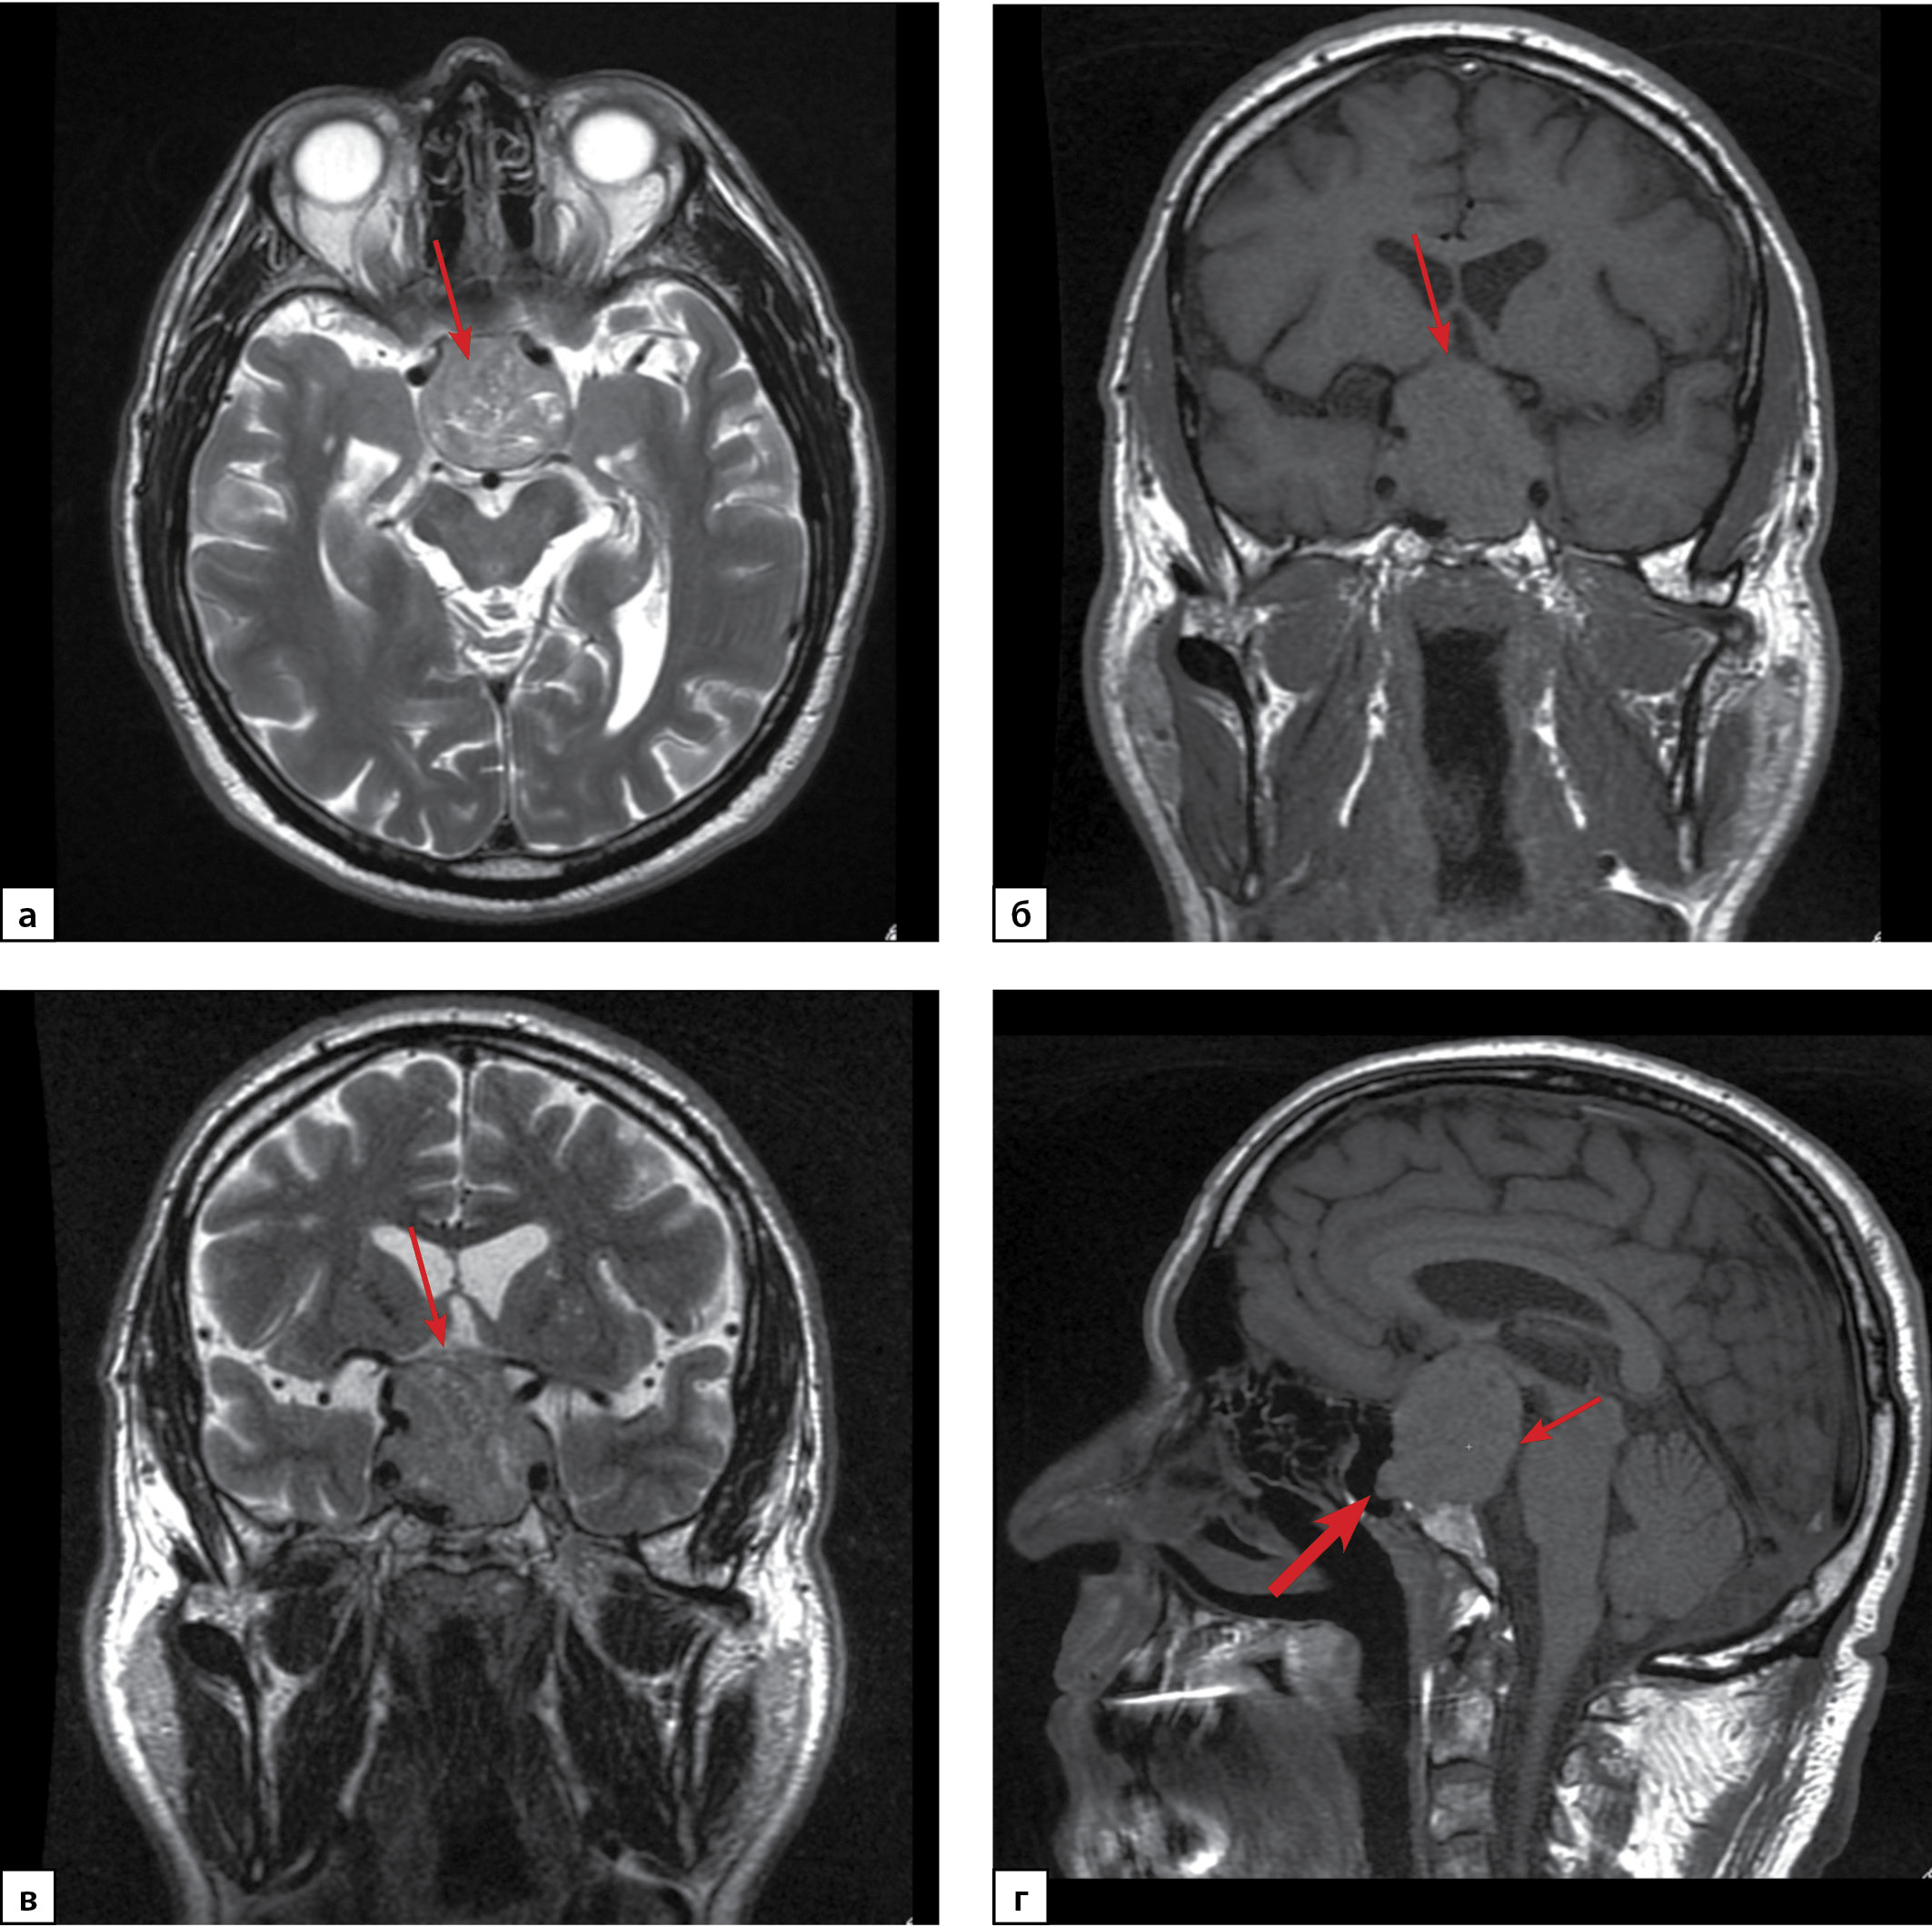

По данным МРТ головного мозга от 17.09.2020 г. на серии сагиттальных, фронтальных и аксиальных томограмм, выполненных в режимах Т1- и Т2-взвешенных изображений (ВИ), в полости турецкого седла определяется образование с четкими ровными контурами, размерами: ширина 40 мм, высота 41 мм, переднезадний размер 33 мм. Структура его неоднородная за счет жидкостных включений. Образование распространяется супраселлярно с компрессией хиазмы зрительных нервов и дна третьего желудочка, прилежит к передним соединительным артериям, латерально в кавернозные синусы с циркулярным окружением кавернозных отделов внутренних сонных артерий (Knosp IV), прилежат к медиобазальным отделам височных долей и прямым извилинам. Кпереди образование пролабирует в основную пазуху, кзади — разрушает спинку турецкого седла и распространяется в предмостовую цистерну с умеренным ее сужением (рис. 1). Неизмененная ткань гипофиза, воронка не дифференцируются. По заключению: макроаденома гипофиза с супра-, инфра-, ретро-, параселлярным (D, S) распространением (Knosp IV).

Рисунок 1. МРТ головного мозга пациента Г. Макроаденома гипофиза с супра-, инфра-, ретро-, параселлярным (D, S) распространением (Knosp IV):

а) Т2-ВИ (взвешенное изображение), аксиальная проекция. Аденома гипофиза (стрелка); б) Т1-ВИ, корональная проекция; в) Т2-ВИ, корональная проекция. Компрессия хиазмы зрительных нервов (стрелка); г) Т1-ВИ, сагиттальная проекция. Распространение аденомы инфраселлярно в основную пазуху (толстая стрелка) и ретроселлярно в предмостовую цистерну (тонкая стрелка).